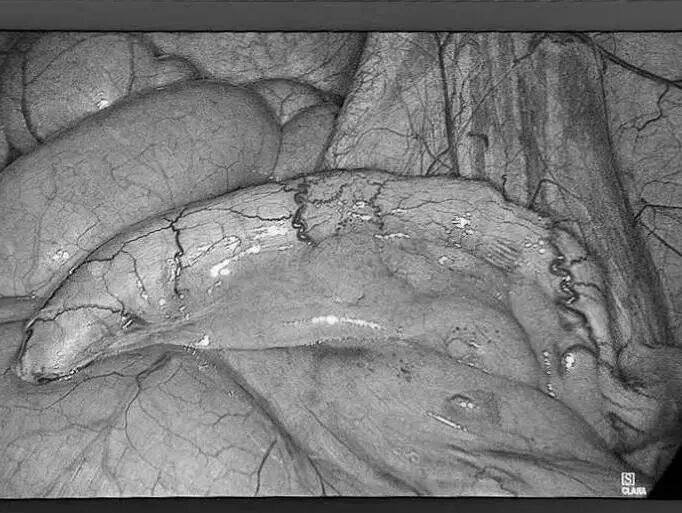

是不是一上厕所就 “见红” 久坐不动后屁股 又痛又痒 别害羞 这可能是痔疮在作怪! 今天贵州航天医院普外科就和大家唠唠这个“难言之隐”,教大家怎么科学应对,轻松告别烦恼! 痔疮是啥? 痔疮不是大病,但遭罪!简单来说,就是肛门附近的血管肿胀了(肛门和直肠部位的静脉曲张),或者是因长期便秘、久坐等原因肛垫被"压垮"了,逐渐下移脱出肛门,里面的血管组织就会像被挤压的海绵一样肿胀起来,形成痔疮。一般分三种: 内 痔:藏在里面,悄悄出血不疼,但擦纸见红要警惕! 外 痔:长在门口,摸得到小肉球,疼起来坐立不安! 混合痔:里外夹击,又出血又疼,简直“雪上加霜”! 这些信号正在提示你: 痔疮可能找上门! 便 血:排便时出现鲜红色血液。 肛门疼痛:排便像“拉玻璃渣”,久坐后更难受! 肛门瘙痒:总想挠,越挠越痒,因分泌物刺激皮肤引起。 脱 出:严重时痔核掉出来。 为啥会得痔疮? 这些习惯你中招没? (一)久坐久站:打工人、司机、老师等群体注意!一坐、一站就是一天,血管压力大! (二)饮食不当:火锅烧烤天天造?菊花火辣辣警告! (三)便秘或腹泻:蹲坑刷手机半小时?肠道抗议了! (四)妊 娠:宝宝压肚子,孕期腹压增高。 (五)遗传因素:家族有痔疮病史?得多留个心眼! 预防痔疮,记住这5招! (一)吃对东西:蔬菜水果粗粮管够,拉粑粑顺畅不费劲! (二)每天多喝水(1500-2000毫升):大便不干硬,菊花少受罪! (三)别当“木头人”:每坐1小时,起来活动5分钟。 (四)养成良好蹲坑习惯:蹲坑时间不得过长,3-5分钟最合适! (五)提肛运动:偷偷练!每天收缩肛门5秒再放松(50次左右),增强肛门肌肉力量。 痔疮能治吗? 方法比你想的简单! (一)轻症自救 1.使用痔疮膏、塞栓剂等药物,消肿止痛。 2.温水坐浴+多休息,促进血液循环,有助缓解。 (二)重症别硬扛 1.微创手术(如吻合器痔上黏膜环切术、激光治疗),创伤小,恢复快。 2.传统手术直接切除痔核。 关于痔疮的3大谣言, 别再信了! (一)“痔疮会自己好?”→拖久了可能更严重! (二)“便血就是痔疮?”→肠癌也会便血,要及时去医院! (三)“手术疼死人?”→现在微创技术创伤小、恢复快,无需过度担心。 出现这些情况,立马去医院! 1.便血止不住。 2.肛门疼到睡不着,走路都困难。 3.掉出来塞不回去,卡住发紫。 痔疮虽常见,但科学防治是关键!管住嘴、迈开腿、别久坐,发现问题早治疗!记住,健康菊花才能让你“畅通无阻”,笑对生活! 注:图片来源于网络,如有侵权,请联系删除。 贵州航天医院普外科专家团队 梁 跃 普外科主任 主任医师 临床擅长:对普外科各类肿瘤手术具有丰富的临床经验。 毕业于遵义医学院,遵义市医学会小儿外科学分会常务委员,遵义市肛肠协会理事,遵义市医学会核医学分会(第二届)委员会委员;荣获第三期“黔医人才计划”优秀学员称号;主持市级课题1项,完成省级课题1项,在国内各类刊物上发表论文10余篇。 钱科洪 普外科 副主任医师 临床擅长:从事普外科临床工作30余年,对各类普外科疾病的诊治、乳腺、甲状腺、胃十二指肠、结直肠等疾病及疑难杂症具有丰富的临床诊疗经验。 毕业于遵义医学院临床医疗系,2009年前往中山大学附属第一医院微创外科进修学习,在国内各专业期刊发表论文数篇。 贵州航天医院普外科简介 基本情况 贵州航天医院普外科成立于1968年,前身属于航天部O61基地3417医院外一科,1998年3417医院、3427医院合并后更名为普外科,下设胃肠外科、肛肠外科2个亚专业科室,拥有专科设备和技术,是中国疝病专科联盟单位,贵州医科大学附属医院胃肠外科专科联盟单位。开放床位40张,配备医护人员21人。 专科特色 普外科致力于胃肠及肛肠疾病的外科临床诊治及科研,以腹腔镜微创外科技术为本,形成以快速康复治疗胃肿瘤、结直肠肿瘤、小肠肿瘤、直肠脱垂、肥胖病、急腹症、各类疝、痔、瘘等专科特色,同时注重胃肠疾病尤其是结直肠恶性肿瘤的基础研究和临床转化研究。 开展手术:腹腔镜下胃癌根治术,腹腔镜下袖状胃切除术,腹腔镜下胃肠道间质瘤切除术,腹腔镜下结、直肠癌根治术,胃癌、结直肠癌的精准治疗,腹腔镜下小儿疝气、成人疝修补术,腹腔镜下阑尾手术,内痔的硬化注射治疗及痔疮的微创治疗:ATH、PPH、TST,直肠脱垂的各种手术治疗,难治性伤口VSD技术,鼻胃肠管、肠梗阻导管置入术,肛肠术后间歇性导尿技术,并引进了中医适宜技术,也为各种化疗患者提供输液港安装,提高患者就医体验。 腹腔镜下腹股沟疝无张力修补术 腹腔镜下腹股沟疝 无张力修补术 腹股沟疝里金斯坦(Lichtenstein)手术 PPH微创术治疗环状混合痔 黏连性或炎性肠梗阻-肠梗阻导管 腹腔镜袖状胃切除 腹腔镜阑尾切除术 腹腔镜阑尾肿瘤切除术 腹腔镜下结肠癌根治术 诊疗范围 胃肿瘤、结直肠肿瘤、小肠肿瘤、肥胖症、各类急腹症、腹部外伤、腹壁疝、便秘、直肠脱垂、痔疮、肛瘘、肛裂等胃肠、肛肠外科疾病。 END